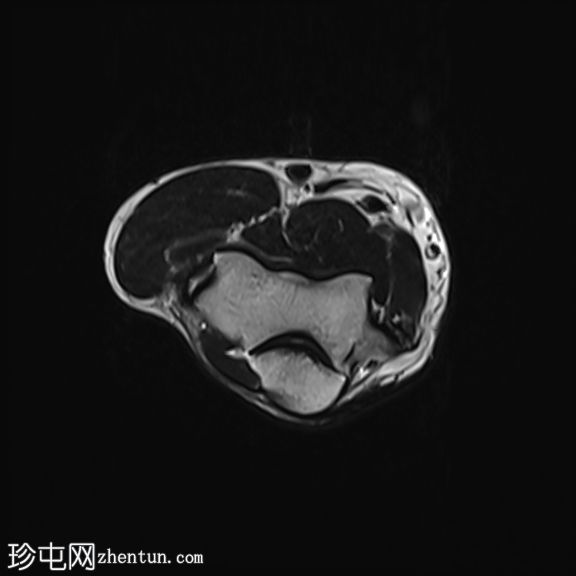

轴位

T2加权像

肘关节伸肌总腱增厚,腱内可见高信号及部分撕裂。伴周围软组织水肿。

本病例展现了网球肘的典型

影像

学特征。